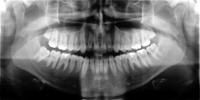

Das Orthopantomogramm ist eine Aufnahme beider Kiefer mit dessen Hilfe der Zustand der Zähne, der Verlauf des Zahndurchbruchs und die Lage der Zahnkeime im Kiefer beurteilt wird.